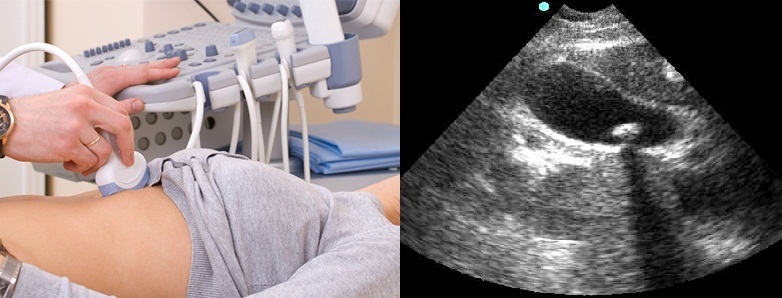

Диагностика калькулезного холецистита в типичных случаях не представляет особых сложностей. Жалобы, анамнез, пальпация, перкуссия…и, для подтверждения, УЗИ органов брюшной полости, как золотой стандарт диагностики ХКХ. При данном исследовании можно обнаружить особенности строения пузыря и протоков, увеличение толщины стенок пузыря, их расслоение, наличие камней в пузыре и протоках и их количество, размер.

УЗИ желчного пузыря